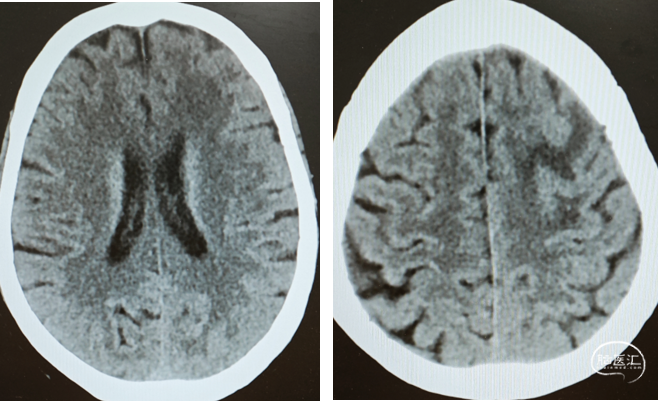

术后第一天复查头颅CT

术后CT